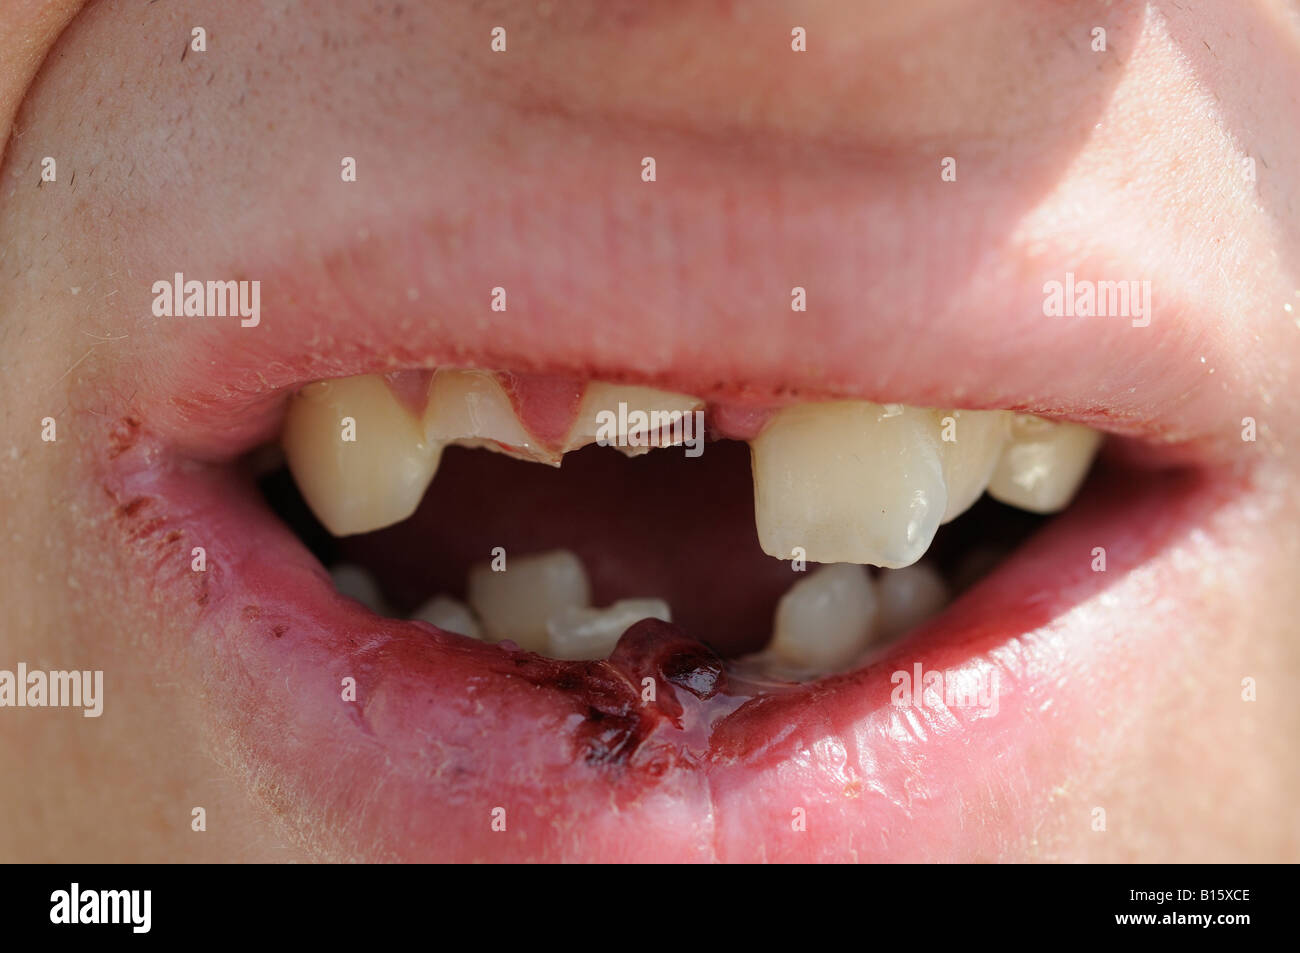

es.dreamstime.comBroken Tooth Stock Photo - Alamy

es.dreamstime.comBroken Tooth Stock Photo - Alamy

www.freepik.esDientes Rotos Y Labio Partido Después De Ser Atacado En Bares

www.freepik.esDientes Rotos Y Labio Partido Después De Ser Atacado En Bares

es.dreamstime.comDientes Rotos Foto De Archivo. Imagen De Roto, Labios - 235894644

es.dreamstime.comDientes Rotos Foto De Archivo. Imagen De Roto, Labios - 235894644